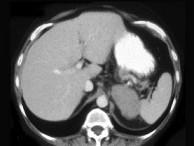

问题 女,47岁,满月脸、向心性肥胖伴高血压1个月,请结合所提供图像,作出诊断()

选项 A.左肾上腺腺瘤 B.左肾上腺腺癌 C.左肾上腺转移瘤 D.左肾上腺嗜铬细胞瘤 E.左肾上腺增生

答案 B